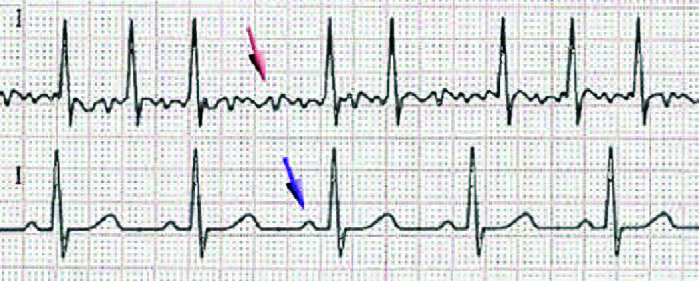

Nei pazienti con Fibrillazione Atriale (Figura 1) ed Osteoporosi bisogna considerare il rischio di riscontrare un ipertiroidismo subclinico.

La terapia deve essere presa in considerazione nei pazienti anziani e nelle donne in postmenopausa con ipertiroidismo subclinico. Alcune evidenze mostrano infatti che la terapia per l’ipertiroidismo ha indotto la conversione a ritmo sinusale spontanea in pazienti con fibrillazione atriale e ipertiroidismo subclinico e che ha portato ad una stabilizzazione / moderato miglioramento dei valori di densità ossea rispetto ai controlli in donne in postmenopausa con ipertiroidismo subclinico.